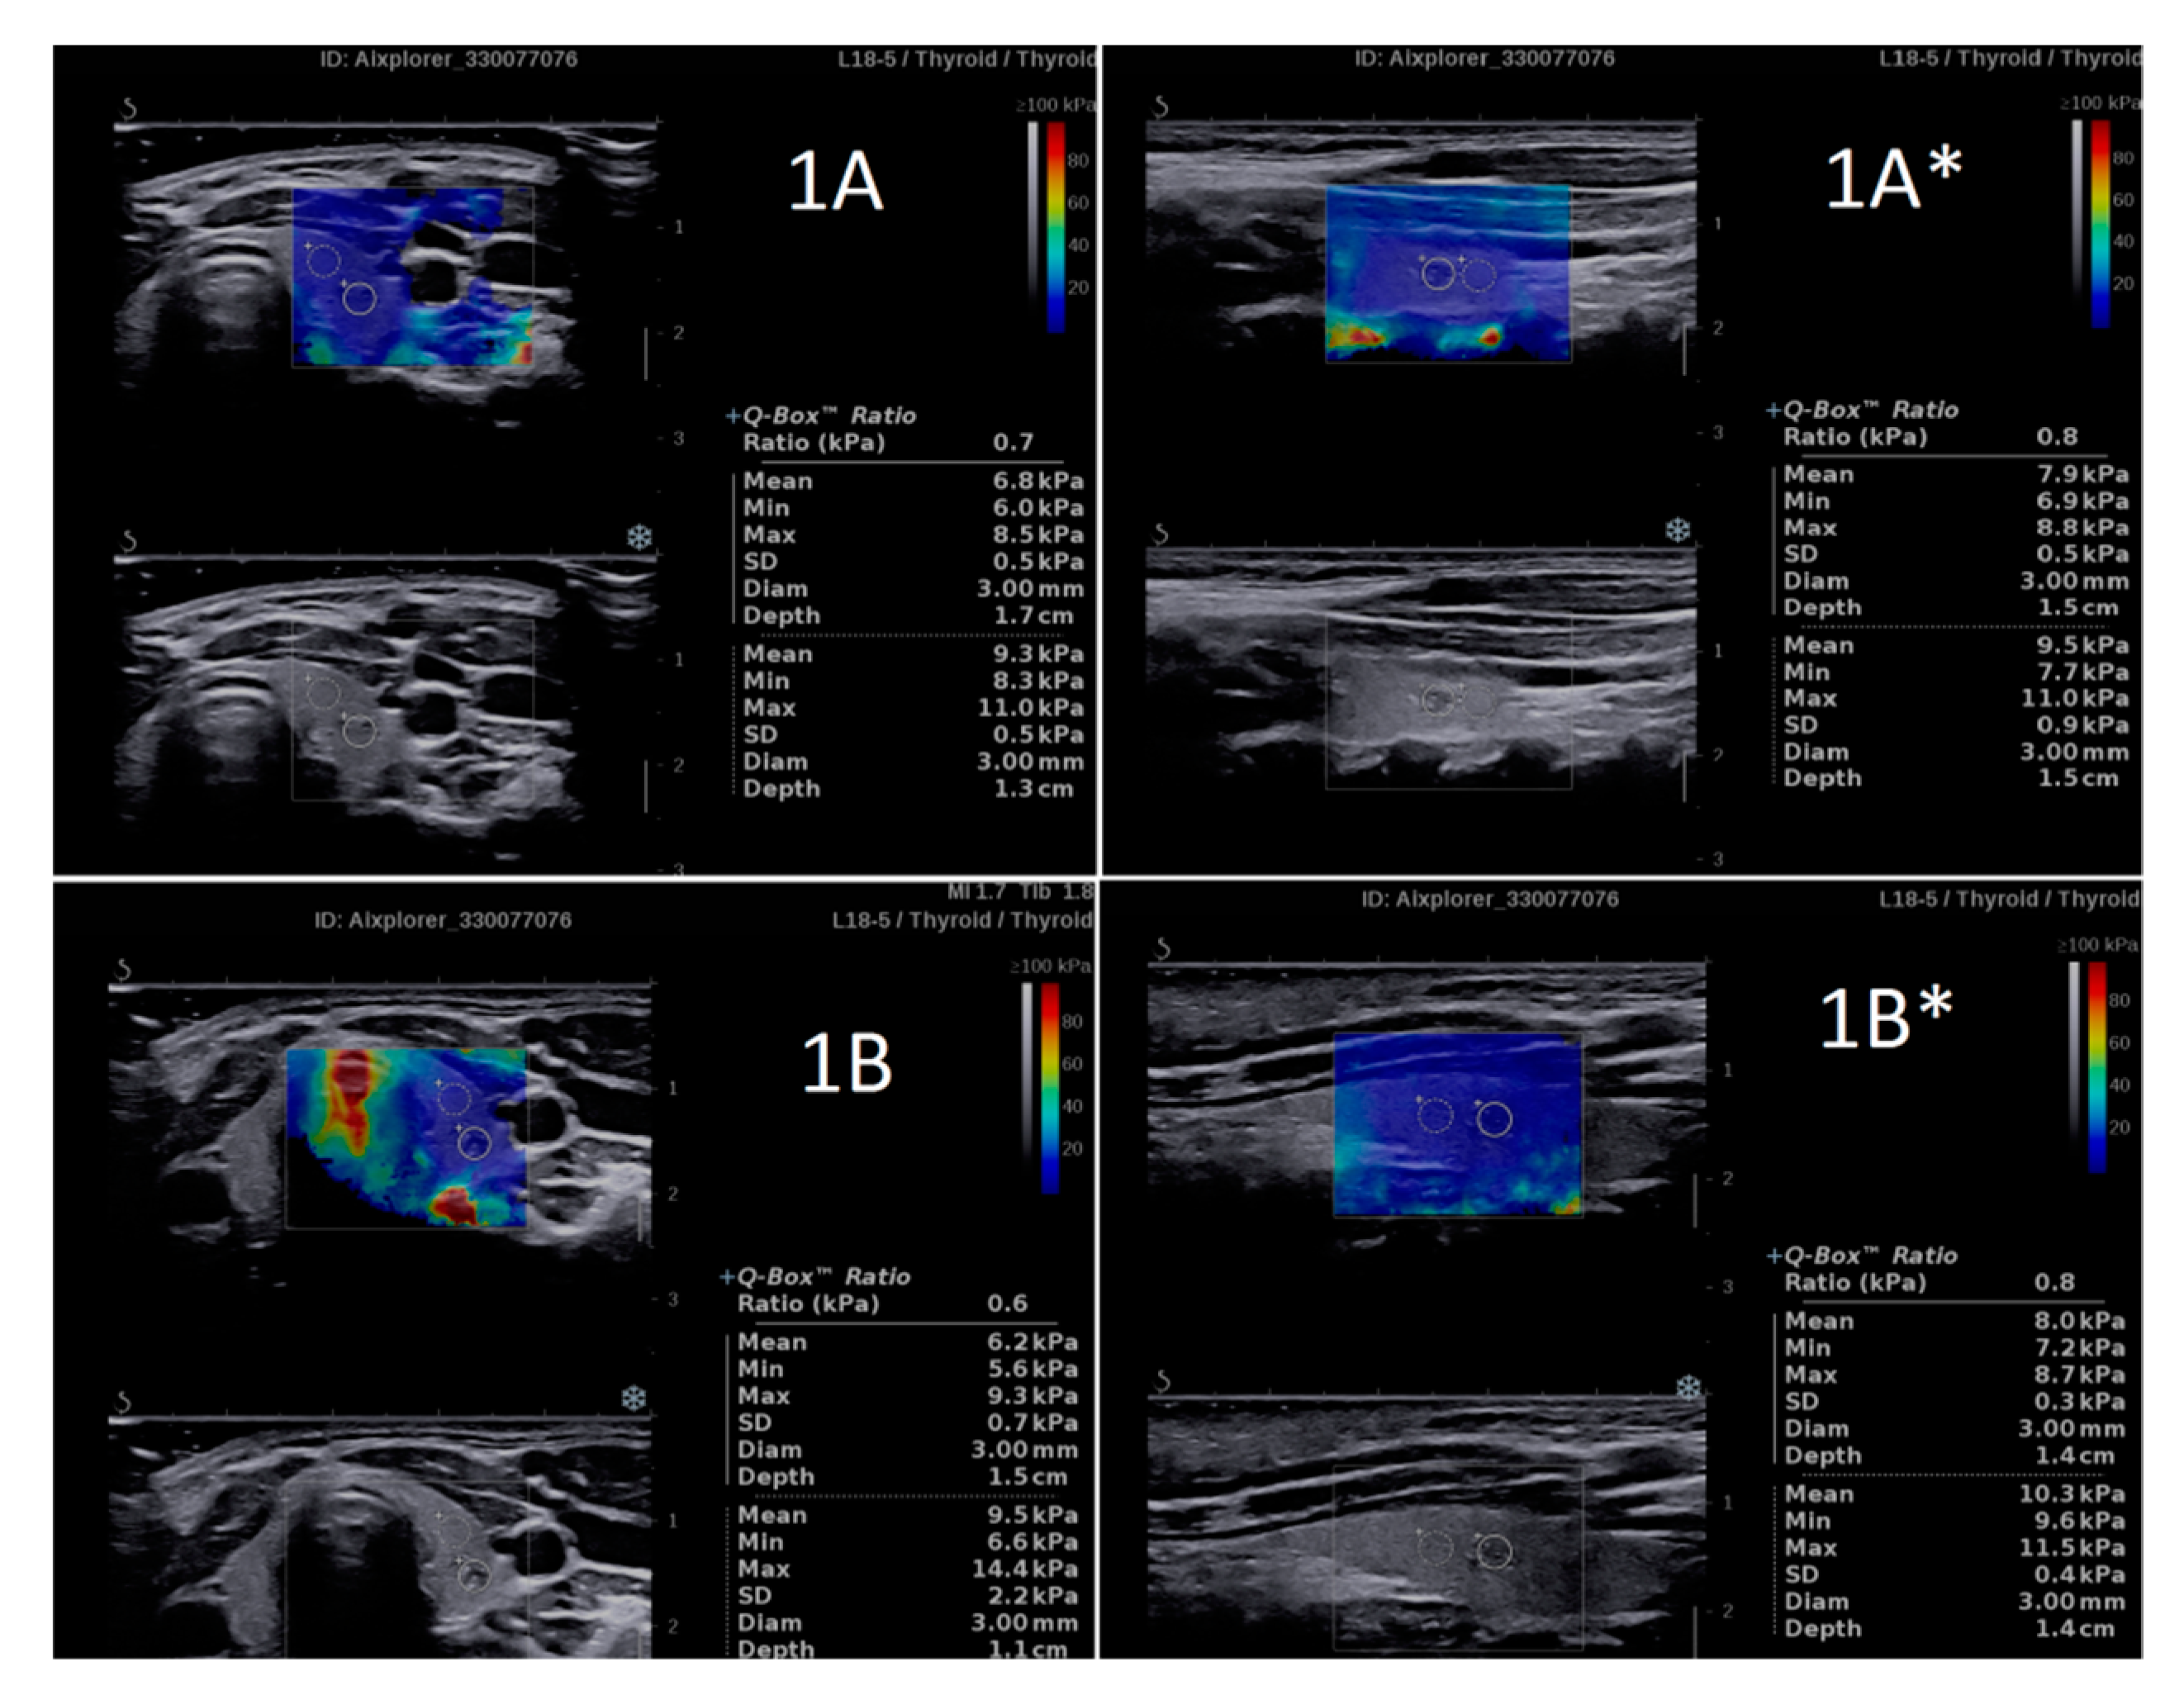

3.2. Intraobserver Variability Related to the Imaging Plane